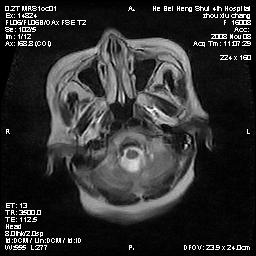

标题: MRI1883:女67岁,半年前曾患脑梗塞,治疗后好转,近3各月精 [打印本页]

标题: MRI1883:女67岁,半年前曾患脑梗塞,治疗后好转,近3各月精

女67岁,半年前曾患脑梗塞,治疗后好转,近3各月精神恍惚。

两种可能:1,转移瘤,2,脑炎,建议增强扫描

多发硬化(年龄不太支持)待排转移瘤

转移瘤?淋巴瘤?

形态及整体病灶看起来首先考虑转移瘤或淋巴瘤,但奇怪的是多个病灶周围均未见显著的水肿区,这不符合这两个肿瘤的特点,结合ct表现及患者病史有个人考虑是否有皮层下动脉硬化性脑病伴多发胶质增生可能.

考虑  皮层下动脉硬化性脑病伴脑炎或

不像占位性病变,考虑脱髓鞘改变

脑转移瘤?

1皮层下动脉硬化性脑病,2胶质增生。

皮层下动脉硬化性脑病伴脱髓鞘改变!

脑白质病

不除外转移瘤,建议增强

支持:皮层下动脉硬化性脑病伴脱髓鞘改变。